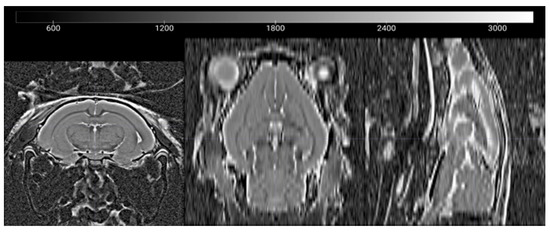

2.2. In Vivo MRI

2.3. Data Processing